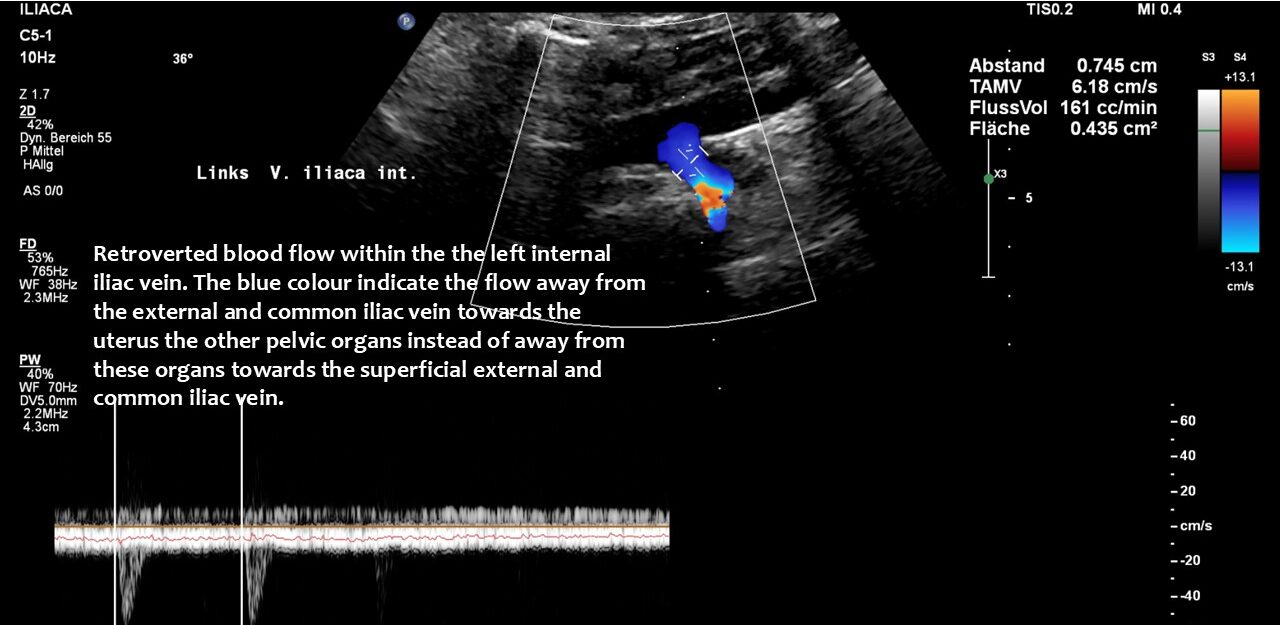

The left renal vein was severely compressed which is often referred to-albeit somewhat misleading-as nutcracker syndrome. The coexisting May-Thurner syndrome further exaggerated the pressurisation of veins in the left pelvic and abdominal hemisphere since the route via the left ovarian vein which usually helps to decrease the pressure inside the compressed left renal vein could not work properly due to the severe counterpressure from the pelvic mouth of the ovarian vein.

The attempt to redirect the pressurised blood from the left renal vein via the left ovarian vein towards the pelvis proved unsuccessful due to the obstructed outflow from the left pelvic hemisphere, a consequence of the compression of the left common iliac vein (May-Thurner syndrome).